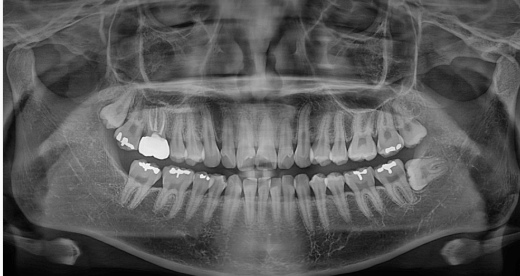

턱 전체를 촬영하는 파노라마 엑스레이는 10μSv로 스탠다드 사진보다 약간 높지만, 여전히 하루치 자연 방사선보다 조금 많은 수준입니다.

치과에서의 엑스레이도 마찬가지입니다. 엑스레이 촬영이 없다면 병의 진행 상태를 정확히 파악할 수 없고,

결국에는 잘못된 치료로 이어질 가능성도 있습니다.

예를 들어, 임플란트를 하려면 턱뼈의 높이, 폭, 신경과의 거리까지 정확히 알아야 하는데,

이를 확인하지 않고 진행하면 부작용 확률이 높아집니다. 이런 상황에서는 오히려 촬영을 안 하는 것이 더 큰 위험을 초래할 수 있습니다.

실제로 저희 병원에서도 엑스레이 촬영 시 의료진은 항상 환자의 상태와 촬영 목적을 먼저 고려한 후, 필요 최소한의 촬영만을 시행합니다.